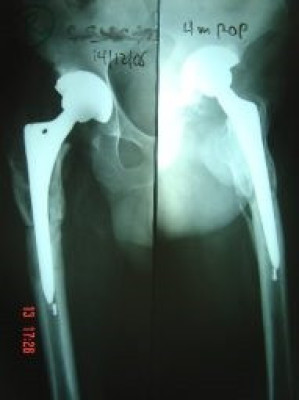

Prótesis Total de Cadera

Envíado por Dr. Ricardo Antonio Gómez G.